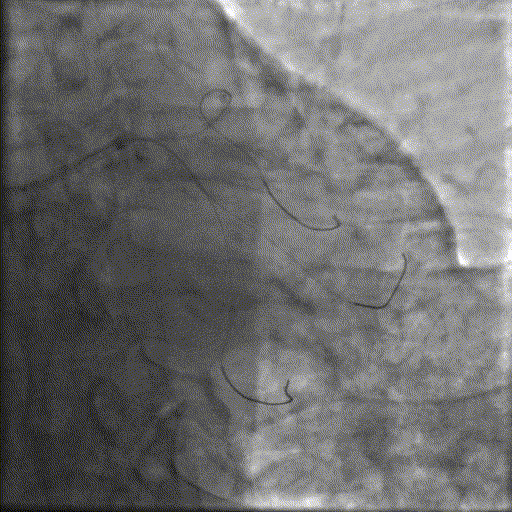

冲击波球囊治疗

3.0x12@4atm 冠脉血管内冲击波导管顺利推送至前降支近端,但无法通过成角钙化处,故于血管近端就地进行10个周期治疗,复查造影见近端狭窄明显减轻;再次选择2.5x12@4atm冠脉血管内冲击波导管推送至成角钙化处,逐步掘进扩张病变并给予冲击波治疗,最终顺利通过成角钙化处,并于前降支中段再次进行10个周期的冲击波治疗。

支架植入并后扩

于LAD近中段串联植入两枚药物洗脱支架,经非顺应性球囊后扩张支架,复查造影及IVUS提示支架膨胀完全,贴壁良好,无夹层撕裂。